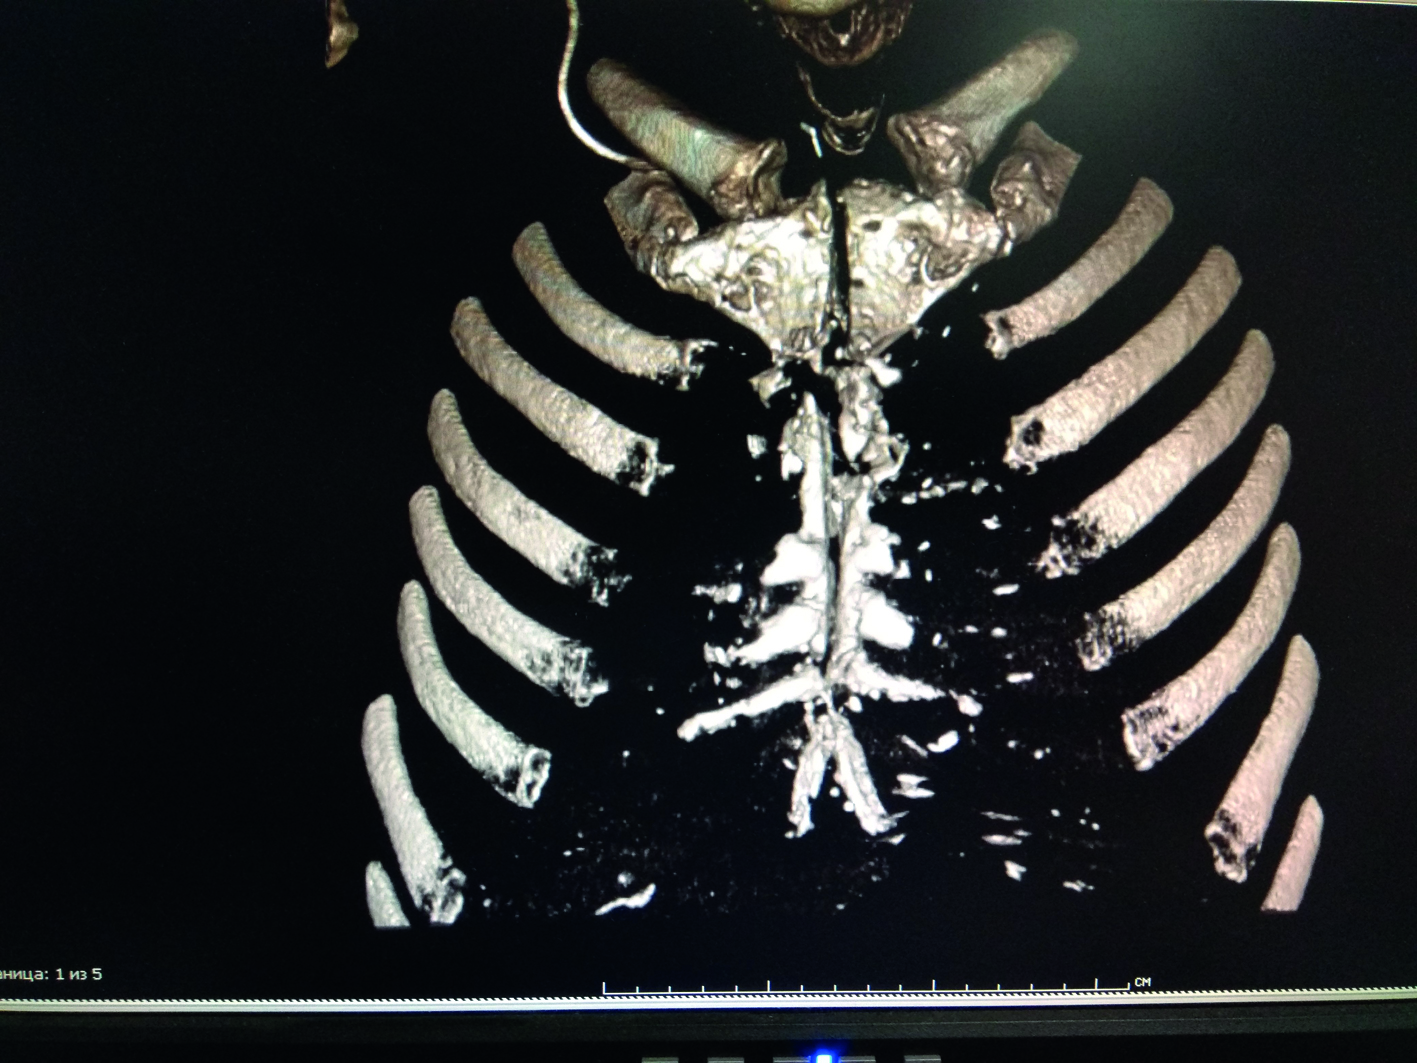

В третьей группе пациентов деструктивные изменения костной ткани (грудина, ребра) до операции были выявлены у 90 (84,9%) пациентов с ПСМ (рисунок 4) и у 25 (86,2%) с остеомиелитом грудины и ребер.

Рисунок 4. Компьютерная томограмма ОГК. Отмечается деструкция и секвестрация створок грудины.

Figure 4. CT imaging of chest. Destruction and sequestration of the sternal cusps.

При этом интраоперационно они были подтверждены только у 106 человек (78,5%). Еще у 9 человек с диагностированной до операции патологией она не верифицирована во время операции. Интраоперационные деструктивные изменения костей выявлены у 104 (98,1%) пациентов с ПСМ и у 13 (44,8%) пациентов с остеомиелитом грудины и ребер (рисунок 5).

Рисунок 5. Интраоперационное фото. Деструктивные изменения в ребре.

Figure 5. Intraoperative photo. Destructive changes in the rib.